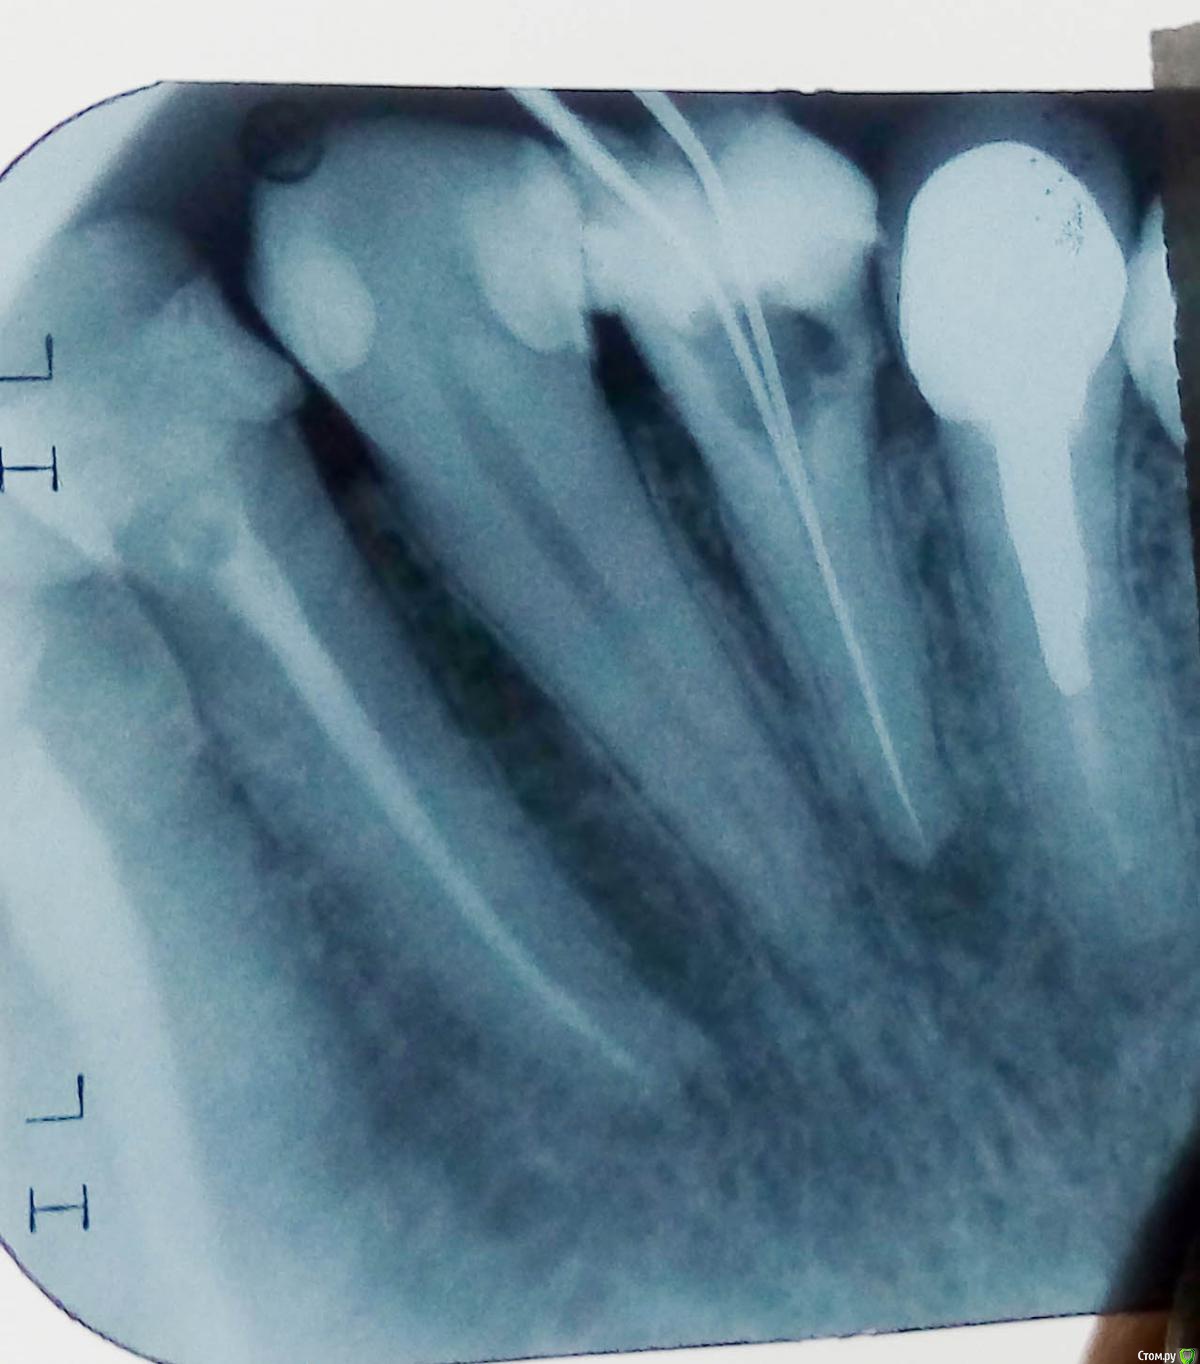

nrjst Опубликовано 31 октября, 2019 Поделиться Опубликовано 31 октября, 2019 Доброго всем! Столкнулся с проблемой. Ночью болел зуб при надавливании. Хоть на утро боль стихла, остался небольшой болезненный эффект при надавливании уже со стороны десны, близ правого крыла носа (чуть ниже и правее). Сходил к стоматологу - сделали снимок () Стоматолог сказал, что это воспаление из-за инфекции. Зуб со штифтом, объемная пломба, и вскрыть,чтобы перелечить не получится.. Если боли будут продолжаться и усиливаться - придется удалять. 3 дня назначил пропить противовоспалительное и подержать соляной раствор во рту, возможно, это поспособствует снятию воспаления и зуб еще послужит... Возможно, есть еще какие-то мнения? Буду рад услышать, поскольку, разумеется, зуб очень жаль терять. Ссылка на комментарий

nrjst Опубликовано 21 ноября, 2019 Автор Поделиться Опубликовано 21 ноября, 2019 (изменено) Был у хирурга. Насчет резекции сказал, что после нее от зуба останется малая часть, и, учитывая штифт с объемной пломбой, не считает данную операцию подходящей в моем случае.. То есть следует удалить и ставить имплант. КТ смотреть не стал, хотя я сказал, что она у меня уже сделана. Я вот не могу еще понять - это киста или что?.. Изменено 21 ноября, 2019 пользователем nrjst Ссылка на комментарий

red_butler Опубликовано 21 ноября, 2019 Поделиться Опубликовано 21 ноября, 2019 Я вот не могу еще понять - это киста или что?.. это хронический апикальный периодонтит 1 Ссылка на комментарий